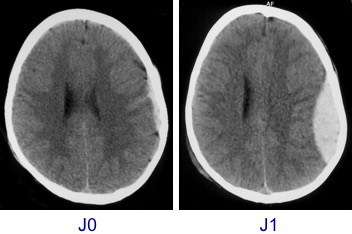

y a-t’il un risque d’hématome extra-dural ?

le risque d’HED secondaire est une préoccupation systématique devant un traumatisme crânien bénin. il est cependant très rare.

la durée convenue du délai de 6 heures ne repose pas sur des bases solides : il s’agit d’un moyen terme entre sécurité et faisabilité pratique. C’est dire l’importance de l’information donnée aux parents lors de la décharge.